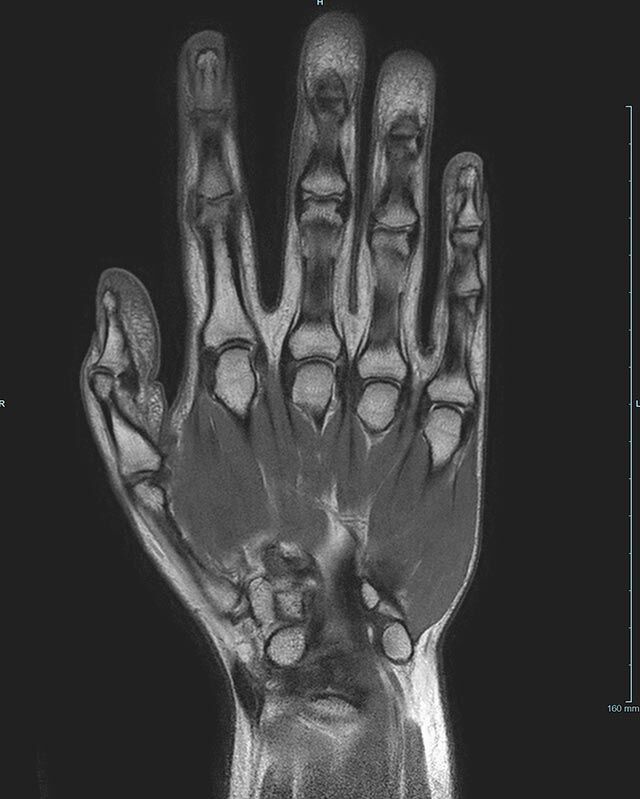

Gelenke

Hand

• Beurteilung von Knochen, Bändern und anderen Weichteilstrukturen der Gelenke nach Unfall.

• Arthrosediagnostik (Knorpelschaden)

• Impingement-Symptomatik

• Ursachenklärung bei wiederholter spontaner Gelenkluxation

• Ausbreitungsdiagnostik bei Gelenkentzündung, z.B. im Rahmen von rheumatischen Grunderkrankungen